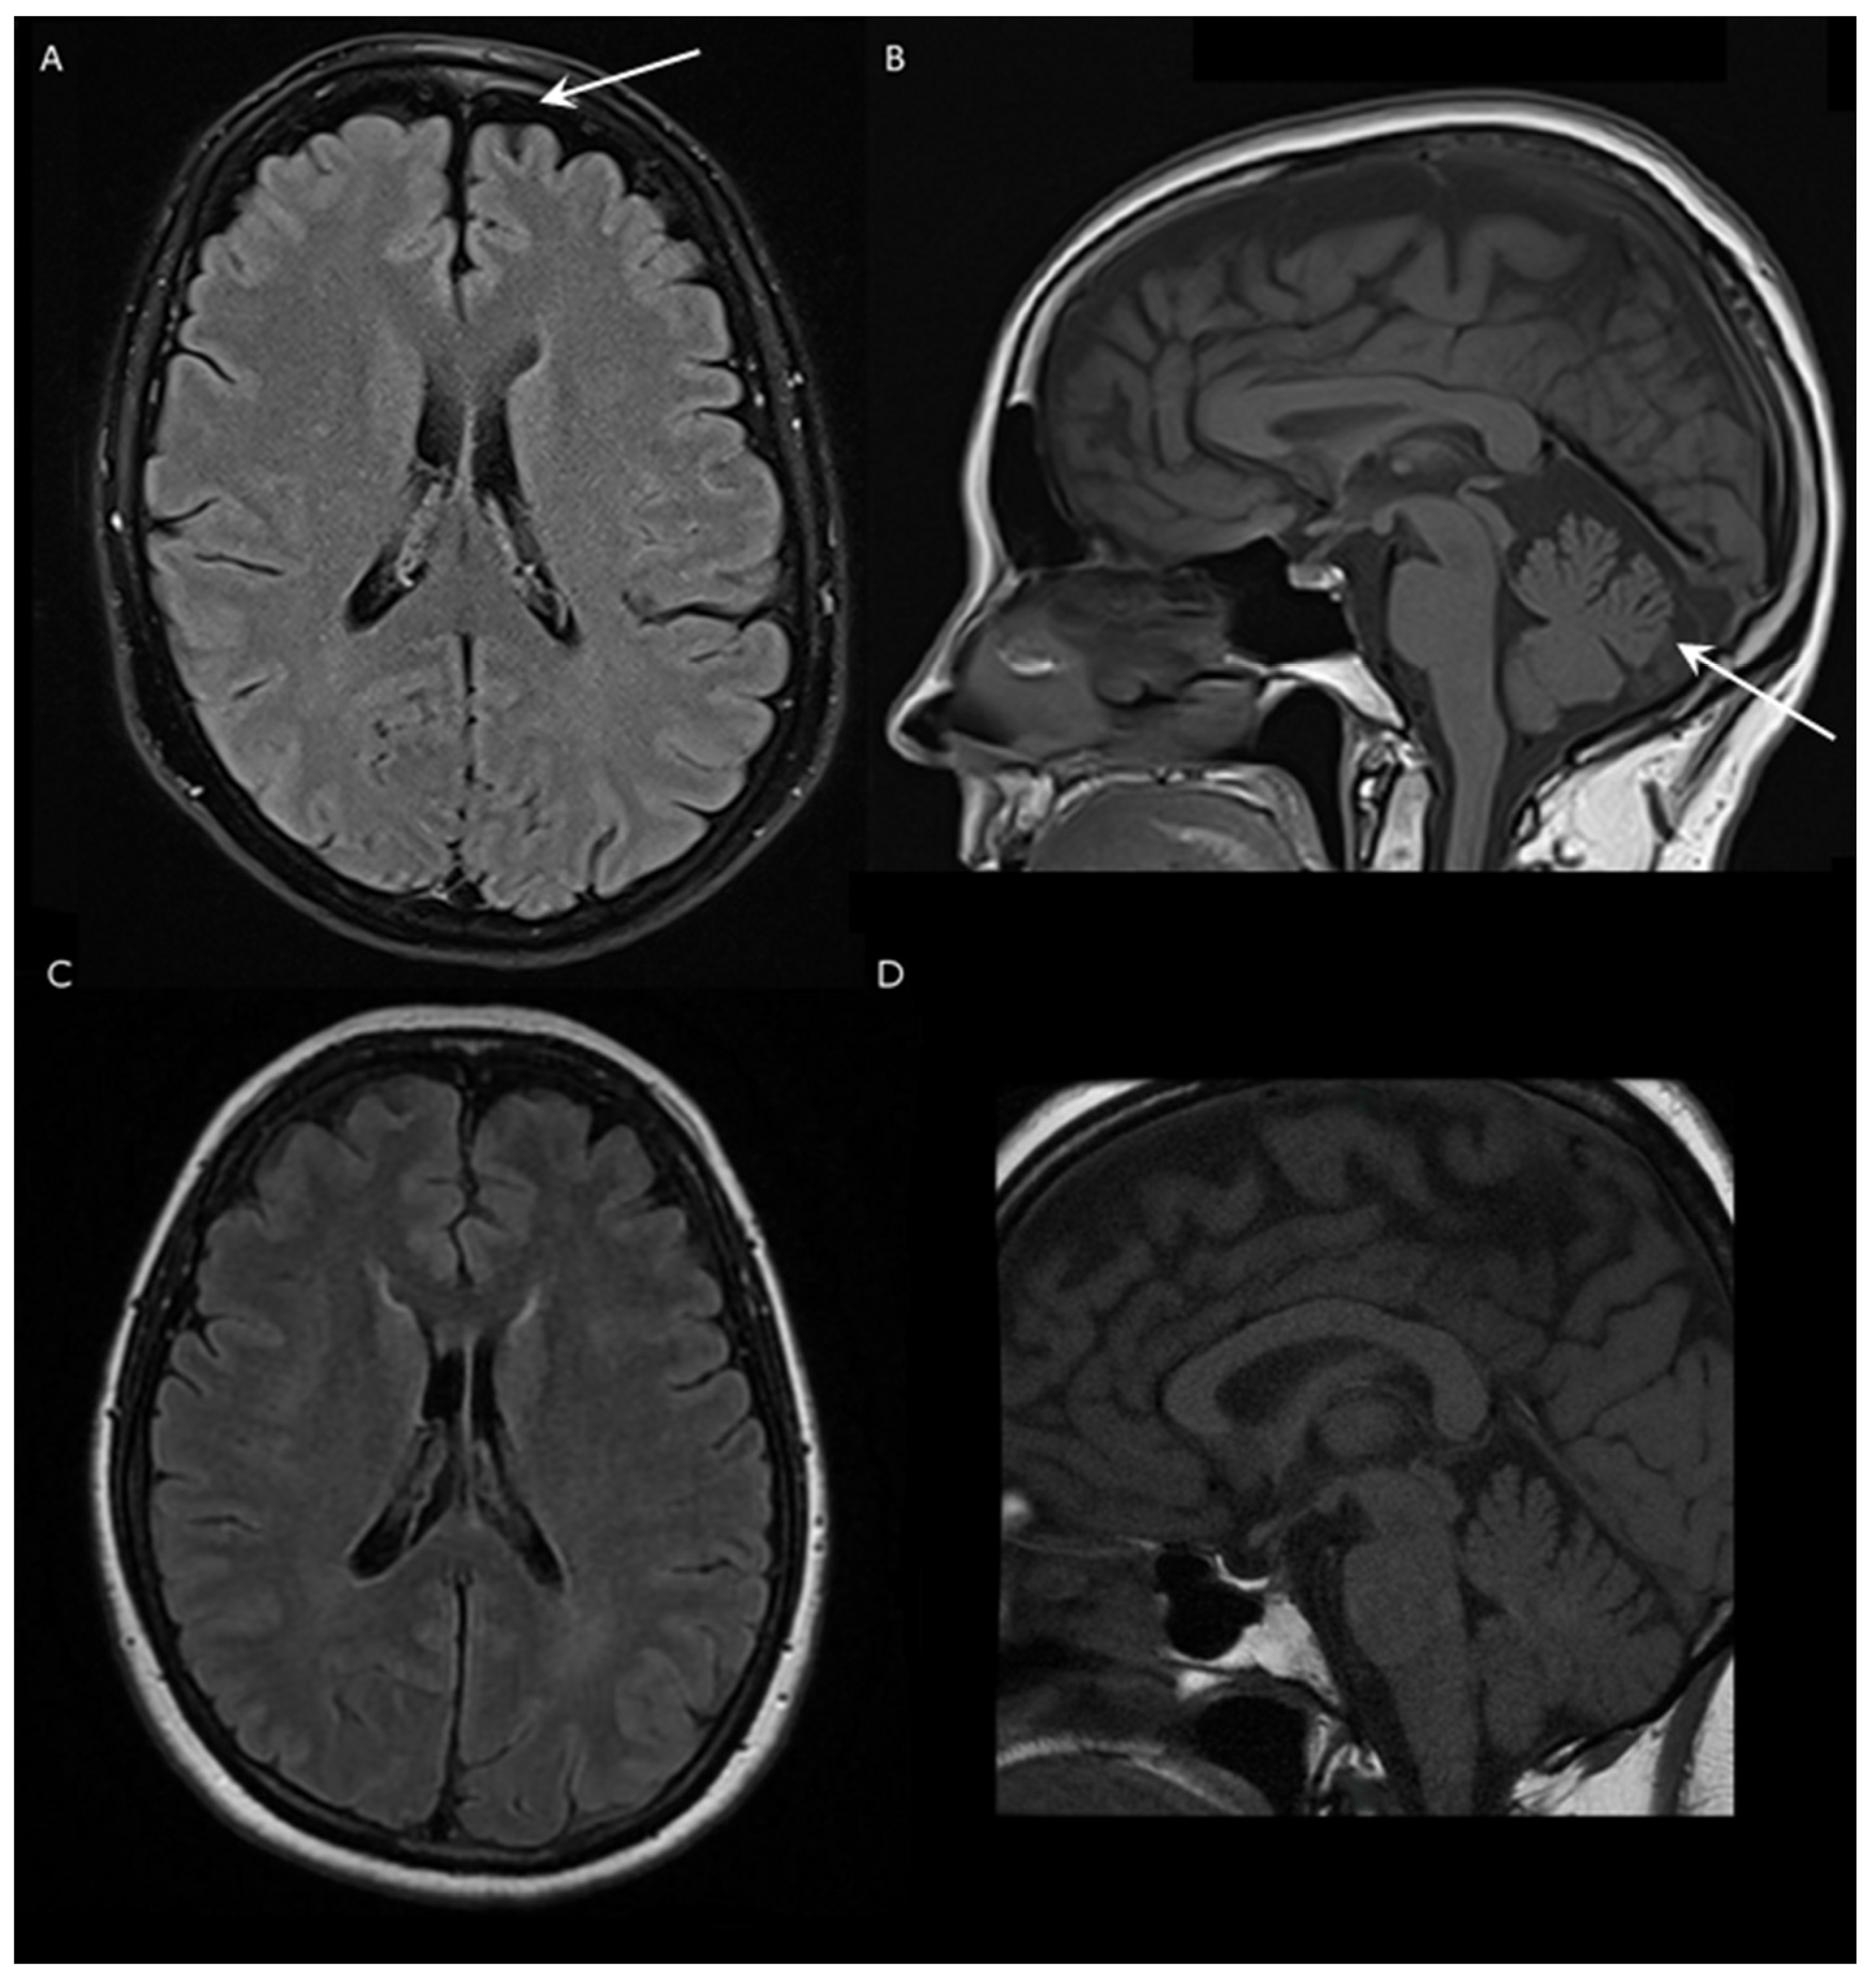

The first complaints of the patient presented in this report were episodic gait disturbance and dizziness at the age of 62. These problems first occurred only in the mornings, the duration of the episodes were 1.5 h; within 2 years, these episodes became longer and sometimes occurred during the afternoon as well. She had divergent strabism from childhood, as well as lumbar discopathy and hypothyroidism, due to Hashimoto thyroiditis. No similar gait difficulty was reported in her family. The neurological examination revealed strabism divergent on the left, horizontal gaze-evoked nystagmus, mild bilateral hypoacusis, slightly excavated feet, moderate spasticity in the ankles, mild paresis in both peroneal muscles, slightly slower fast alternating movements in the feet, mild gait ataxia, dysmetria and intention tremor in the upper limbs, slight ataxia in the lower extremities and discrete vibration hypesthesia in the feet. Dysarthria, ocular dysmetria, hyperreflexia, Babinski sign and extrapyramidal symptoms were not observed. The Scale for the Assessment and Rating of Ataxia (SARA) of the patient was 5 out of 40 in 2021, and the score did not progress during the following year. Nerve conduction studies did not detect polyneuropathy. Brain MRI examination showed mild cerebellar atrophy with vermian predominance and shrinkage of the frontal lobe with similar severity (Figure 1). Additionally, a small T2 hyperintense, T1 hypointense lesion was detected in the corpus callosum; however, its size decreased in the last 2 years. The spinal cord MRI did not demonstrate myelopathy. The video head impulse test revealed decreased vestibulo-ocular reflex on the left side and positional nystagmus on the right side. The cervical vestibular evoked myogenic potential test was absent on the right side and normal on the left side. Brainstem auditory evoked potential was normal. Detailed laboratory investigation did not detect obvious secondary etiology in the background of the ataxia. Serum levels of creatine kinase, albumin, B12, folic acid and alpha fetoprotein were all normal as well. The ANA, anti-TPO and antichromatin antibodies were positive in the last 2 years.

Figure 1.

Brain magnetic resonance imaging (MRI) of a Hungarian SCA40 patient and an age-matched healthy subject. (A) Fluid-attenuated inversion recovery (FLAIR) axial and (B) T1-weighted sagittal scans of the patient. The arrows indicate the frontal lobe and cerebellar atrophy, respectively. (C) FLAIR axial and (D) T1-weighted sagittal images of a healthy age-matched female.

The clinical phenotype of the subject is characterized by slowly progressive episodic mild cerebellar symptoms, slight spasticity in the ankles and vibration hypesthesia in her feet. Similar neurological abnormalities were described in a Chinese family, although with more severe signs, which is supported by the difference in the SARA scores as well (Supplementary Table S1) [3]. Except mild spasticity in the ankles, no other upper motor neuron symptoms or movement disorders were noticed in the patient described in this case, although these neurological alterations were frequently observed in other cases [5,6,7,8,9,10]. Brain MRI examination showed mild cerebellar and frontal lobe atrophy, but no brainstem shrinkage, bilateral olivary degeneration or any other specific structural alterations were found.